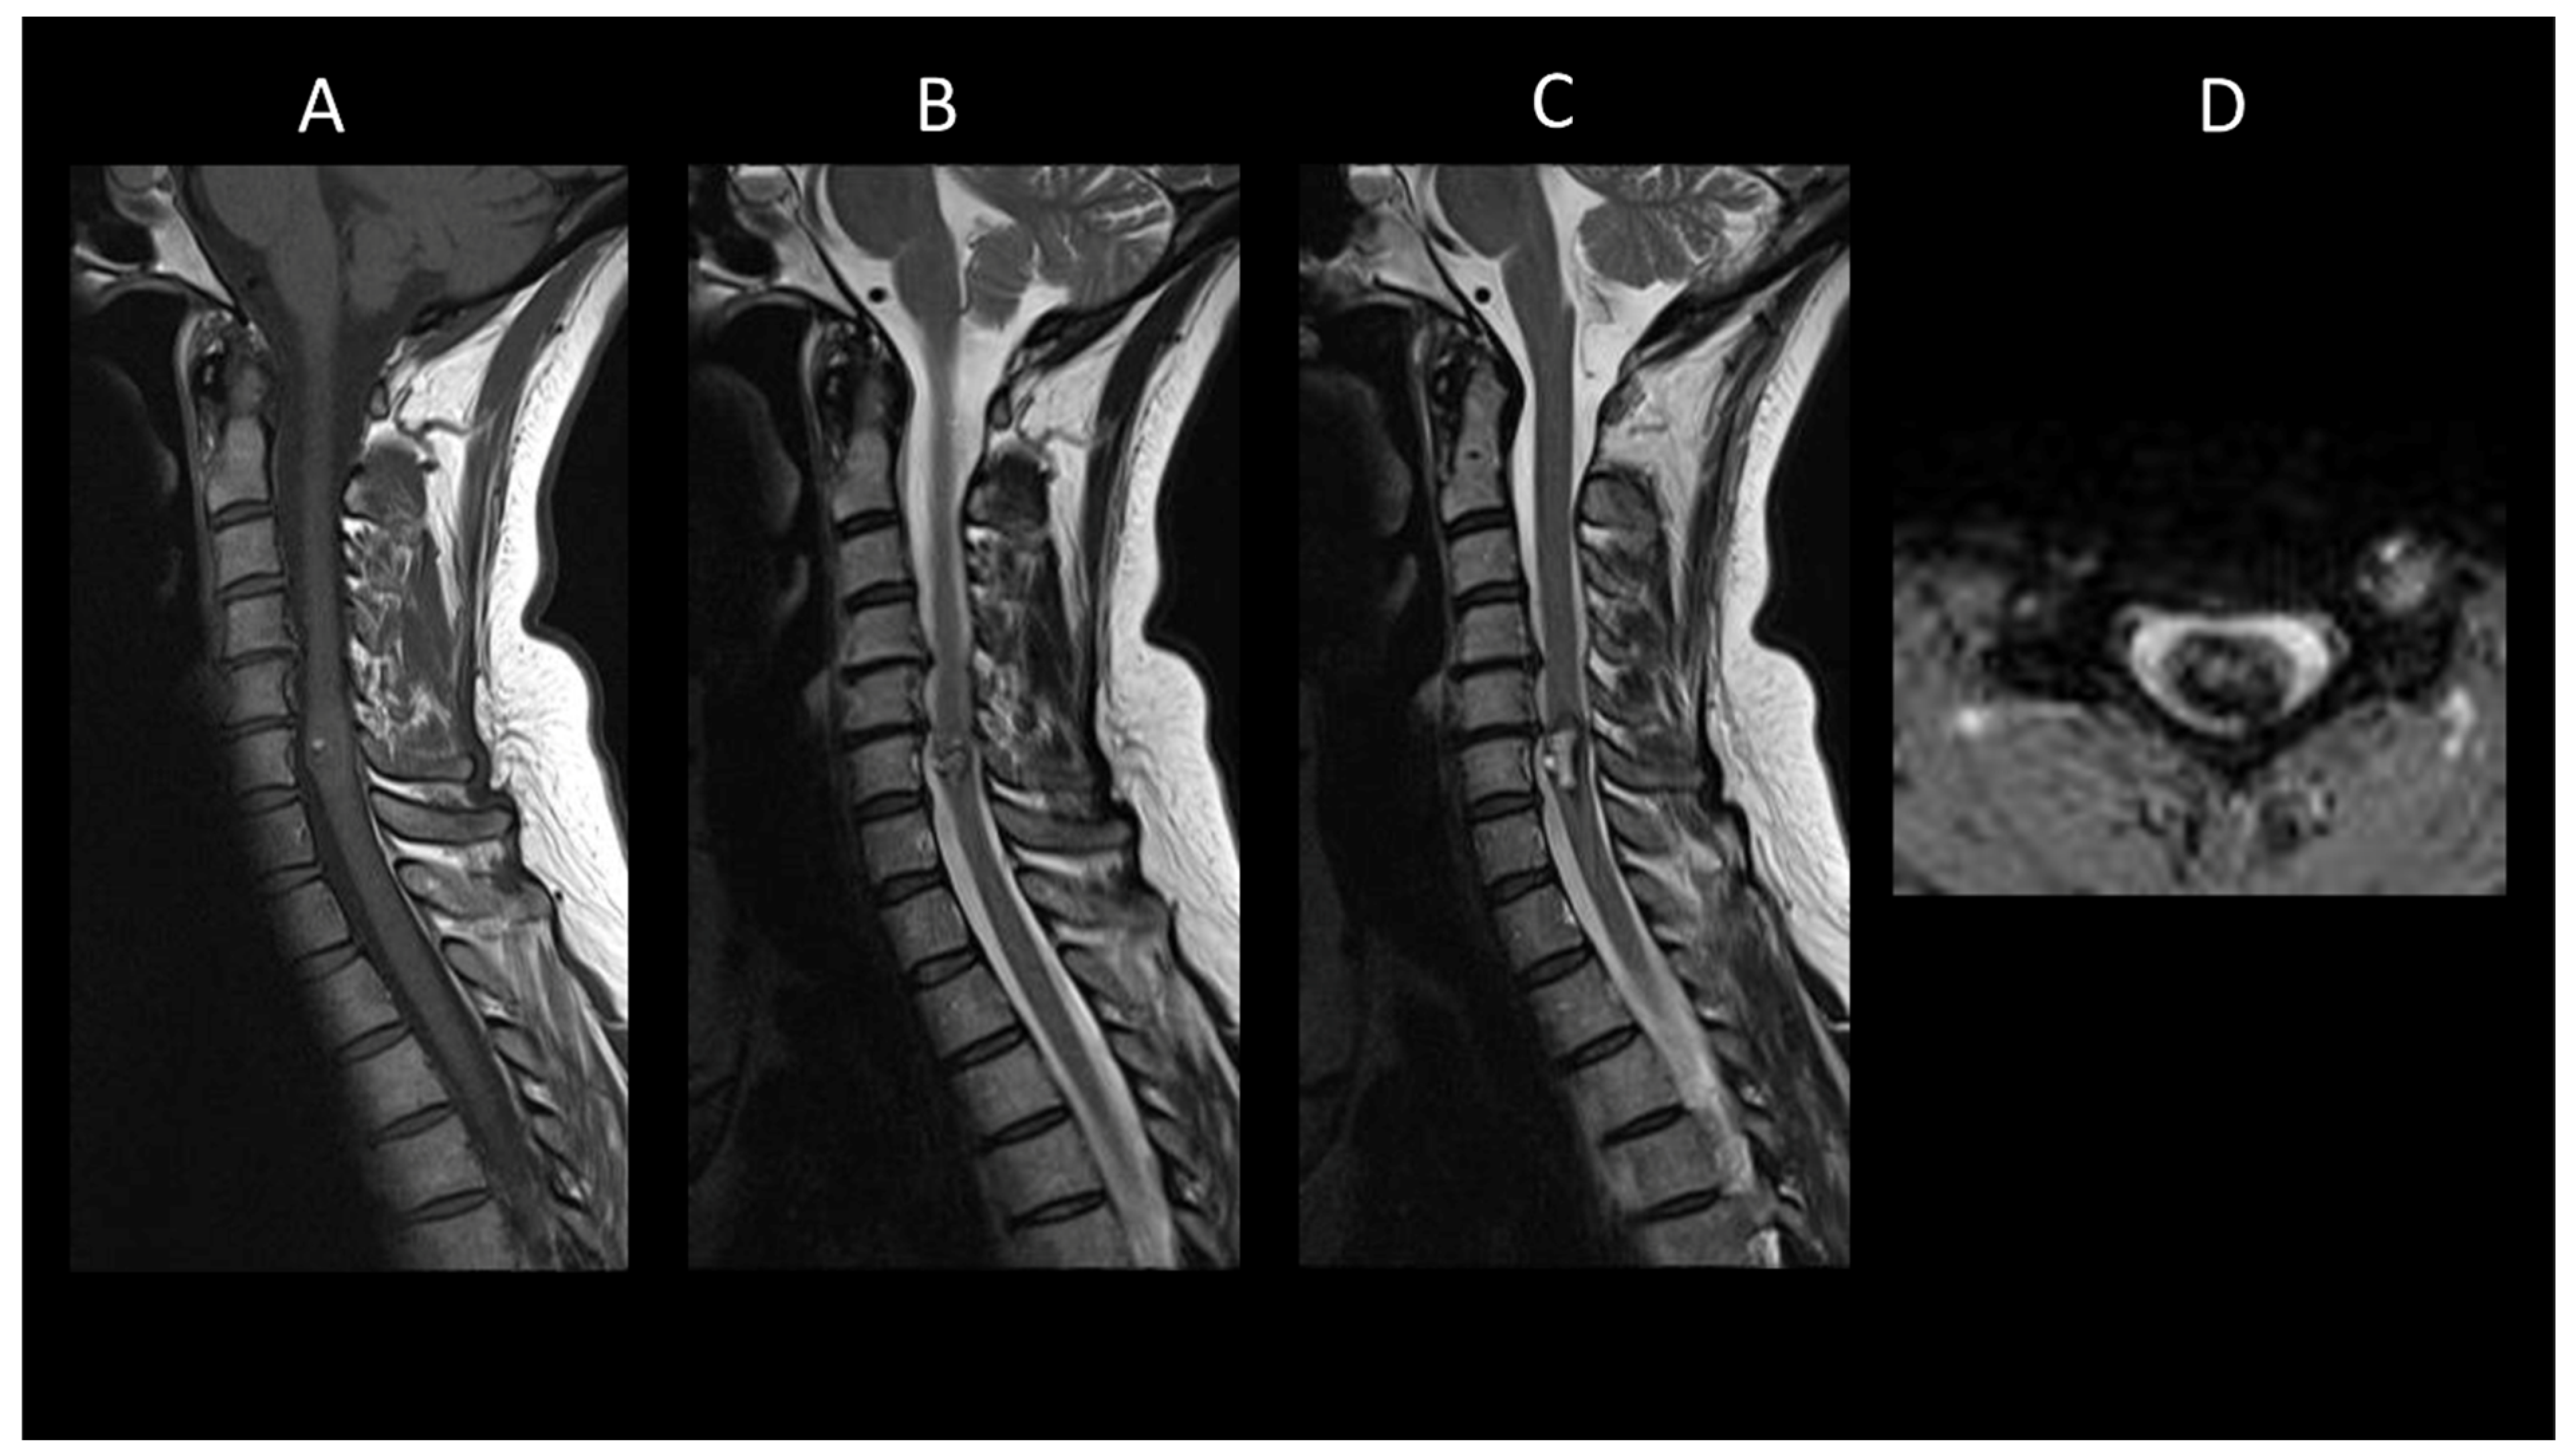

3.2. Degenerative Compressive Myelopathy

- Flanagan, E.P.; Krecke, K.N.; Marsh, R.W.; Giannini, C.; Keegan, B.M.; Weinshenker, B.G. Specific Pattern of Gadolinium Enhancement in Spondylotic Myelopathy. Ann. Neurol. 2014, 76, 54–65. [Google Scholar] [CrossRef]

- Syc-Mazurek, S.B.; Montenegro, M.; Clarke, M.J.; Flanagan, E.P. MRI with Neck Extension to Diagnose Cervical Spondylotic Myelopathy. Pract. Neurol. 2022, 22, 162–163. [Google Scholar] [CrossRef] [PubMed]